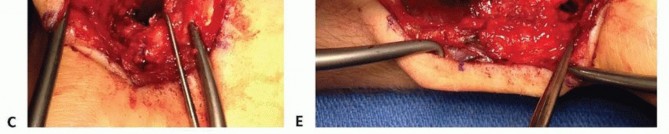

To mobilize the pedicle safely, the retinaculum must be unroofed. The critical technical pearl here is to avoid cutting directly over the artery. Instead, the retinaculum is incised longitudinally over the radial aspect of the first dorsal compartment (exposing the APL and EPB) and over the ulnar aspect of the second dorsal compartment (exposing the ECRL and ECRB). By elevating these retinacular flaps toward the midline interval, the surgeon creates a continuous, robust strip of retinaculum that contains the 1,2 IC SRA safely within its substance. This perivascular cuff of tissue protects the delicate microvasculature from sheer stress and preserves the vital venous drainage network.

The debridement must be aggressive and uncompromising. The surgeon must excavate all necrotic, sclerotic, and fibrous tissue until healthy, punctate bleeding bone is encountered in both the proximal and distal fragments—the so-called "paprika sign." If the proximal pole is truly avascular, it may not bleed vigorously, but the sclerotic margins must still be resected to expose the underlying trabecular network, allowing the incoming vascularized graft to integrate. During this debridement, the surgeon must be careful to preserve the volar cortical hinge of the scaphoid, if intact, to maintain anatomical length and prevent destabilization of the construct. Once the defect is fully prepared, its dimensions are carefully measured using a sterile caliper to guide the subsequent graft harvest.

Graft Harvest and Inset